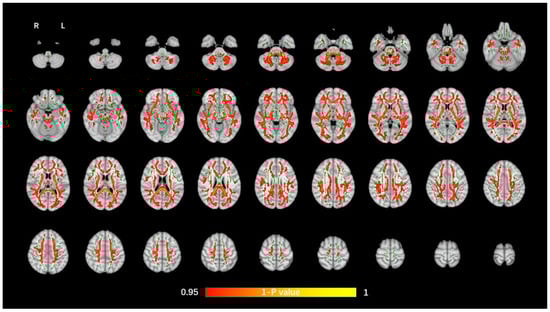

The average FA WM skeleton of all subjects was constructed in TBSS analyses, as shown by the green line in Figure 1, Figure 2, Figure 3 and Figure 4. An analysis of variance of voxel level was carried out on the WM skeleton, and the differences among the three groups were compared. p < 0.05 after FWE correction based on TFCE was statistically significant. Statistically significant areas were expanded to better show the position of WM fiber bundles, as shown in the red part in Figure 1, Figure 2, Figure 3 and Figure 4. The statistical results showed that the DTI indexes of most fiber bundles were statistically significant. There was a significant statistical difference in the FA, MD, AD, and RD values of the FMI, FMA, IFOF, SLF, ILF, ATR and corticospinal tract (CCT) among the three groups (p < 0.05; Figure 1, Figure 2, Figure 3 and Figure 4).

Figure 2.

Voxel-wise TBSS analysis results of MD images among the WML-VCIND, WML-VaD, and HC groups. Green represents the mean WM skeleton of all subjects. Red-yellow (thickened for better visibility) represents regions with a significant F-test statistical difference (p < 0.05, TFCE-based FWE-corrected). TBSS, tract-based spatial statistics; MD, mean diffusivity.